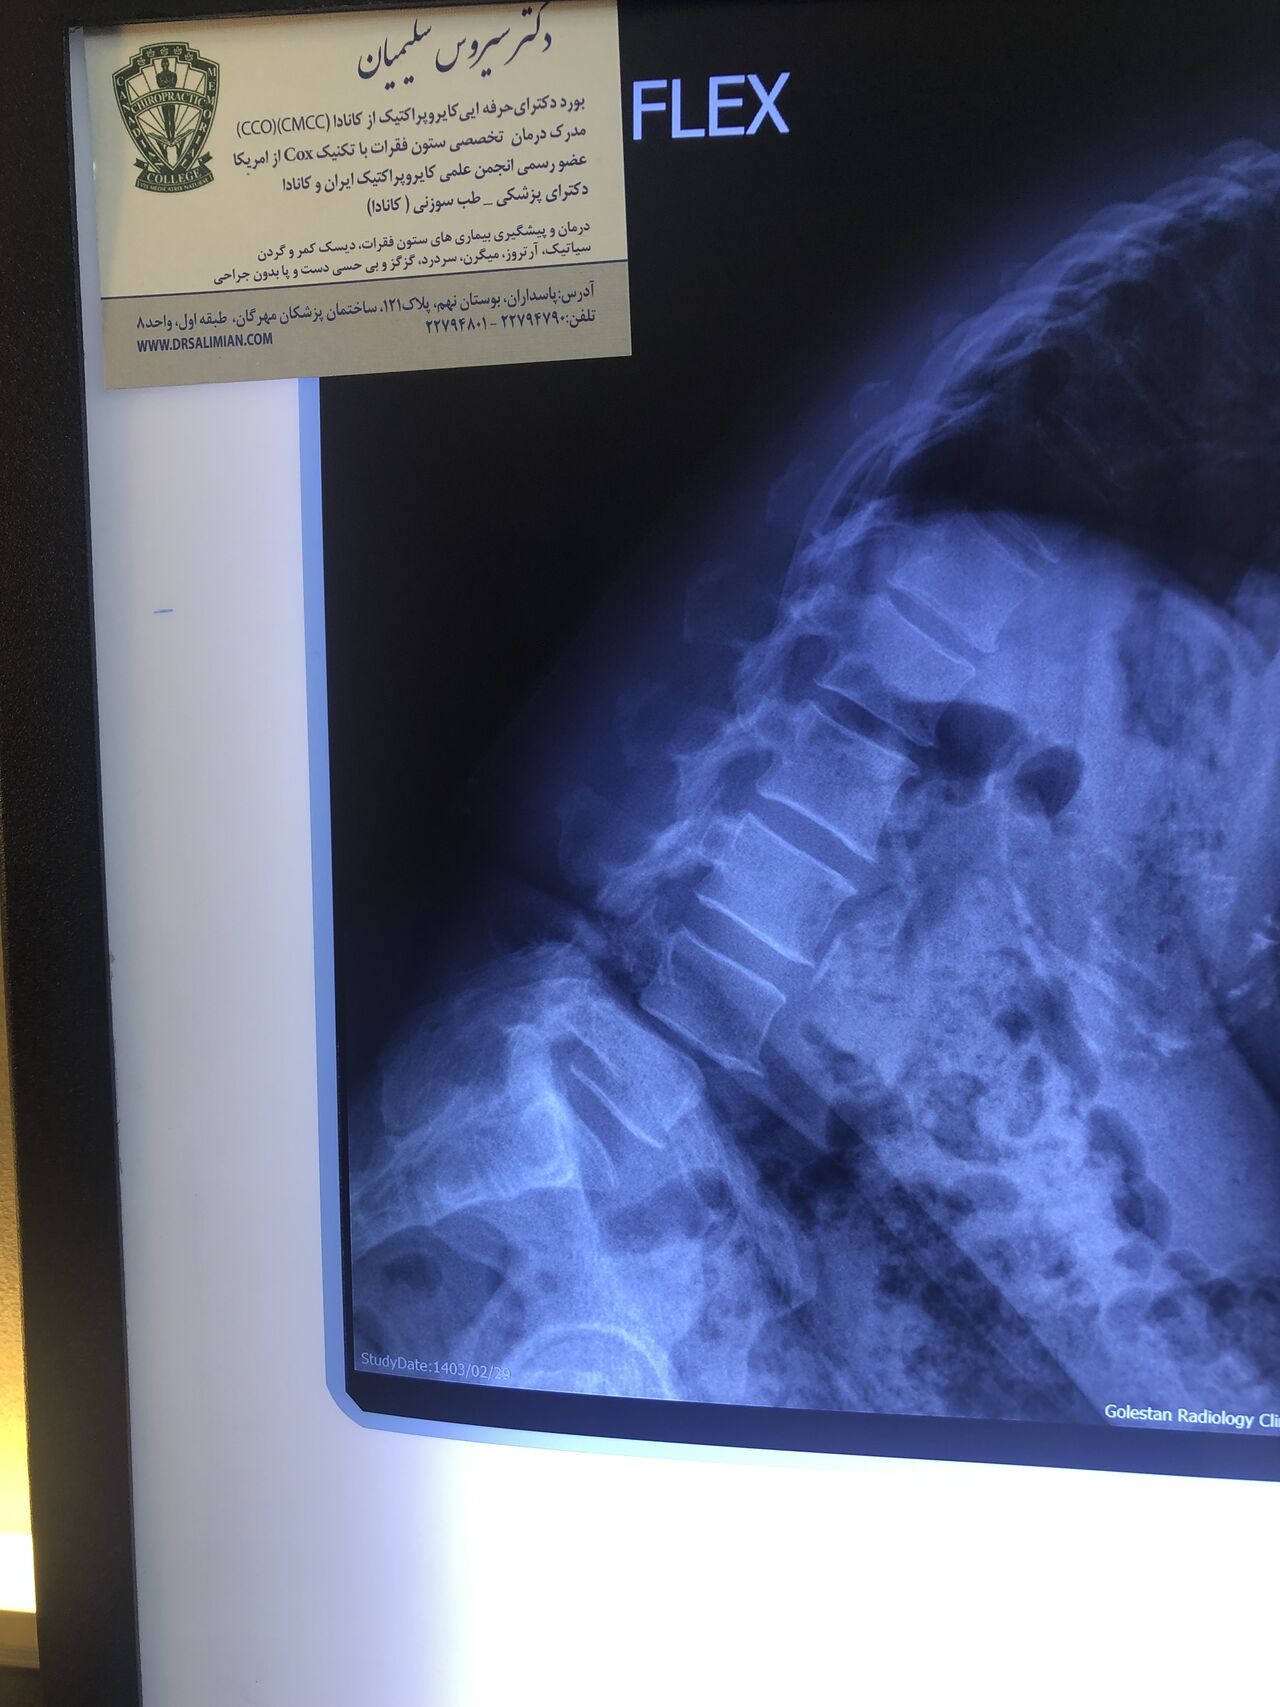

Since I’ve noticed instability in some segments I asked for dynamic L/S x ray:we see mild L4 ant listens due to DjD/DDD. There is not any pars defect.

This time presented to my cl with LBP mainly during sleep at night. Just brought me her mri. According to her mri I ordered dynamic L/S X. R.

Is ant listhesis of L4 unstable or stable?

59 yrs old female today was presented to my office few days ago with low back pain in walking. Had history of fall 4 years ago which was resulted in L 3 fracture. She had sement injection in L3.

I ordered DEXA ( had osteopenia in hip) and dynamic lumbar spine x ray Please mention what would be your plan of management. If you decide to give her treatment what kind of treatment(adjustment or decompression or other treatments)whould be suitable for her? Doctors of chiropractic can decide and come up with good plan of management and treatment for these patients and are well trained when they have to refer these patients for surgery or pain management clinics. Proper selection of these kind of patients is another important fact that can be done precisely by chiropractors.